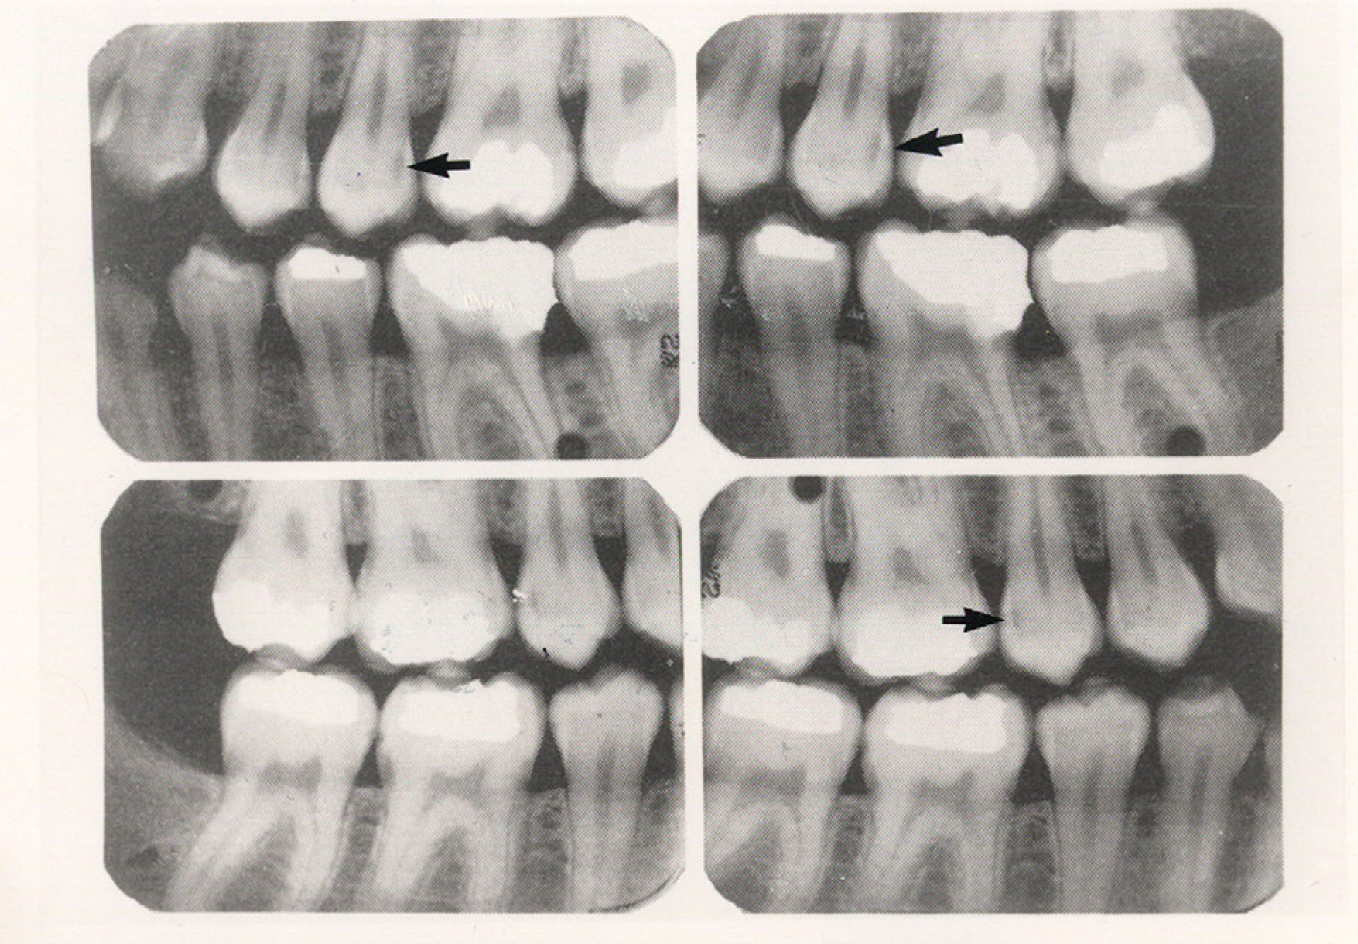

Bitewing examinations were introduced by Dr. Raper in 1925. Bitewing images focus on the clinical crowns of both the maxillary and mandibular teeth. Bitewings do not show the apices of the tooth and cannot be used to diagnose in this area. The greatest value of bitewing radio- graphic images is the detection of interproximal caries in the early stages of development, before it is clinically apparent. The arrows in Figure 2 indicate areas of interproximal caries. Bitewing images also reveal the size of the pulp chamber and the relative extent to which proximal caries have penetrated.

Figure 2 - Bitewing Images

Figure 2